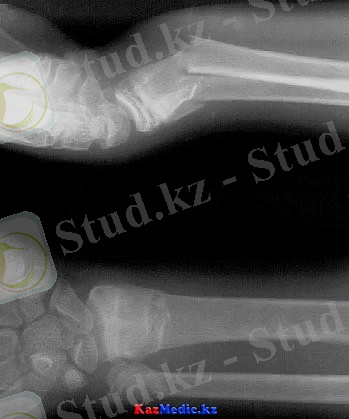

Білек сүйектерінің төменгі метаэпифизігнің сынықтары